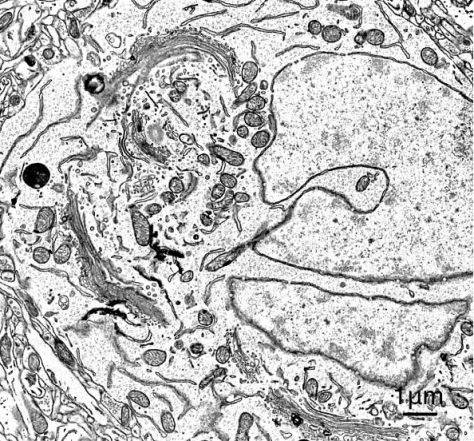

| Electron Optics | Resolution | 1.5 nm@1 kV SE | 1.8 nm@1 kV BSE | 1.5 nm@15 kV BSE |